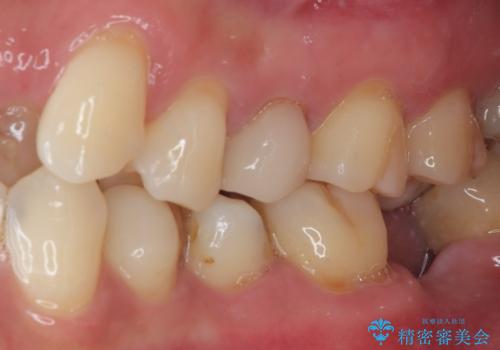

見た目、機能面共に大変喜んでいただきました。

歯と歯の間の虫歯をコンポジットレジンや保険のメタルインレーで治すと段差ができたりして清掃性が悪くなるので、セラミックインレー修復やゴールドインレー修復などの適合の良い詰め物で治療することをオススメします。